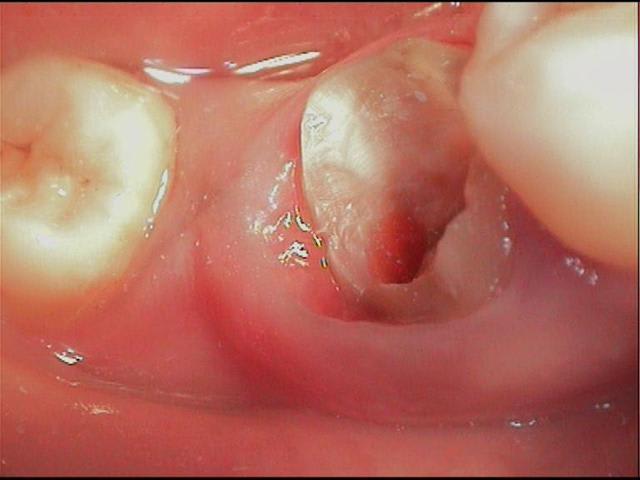

en déposant délicatement le compo, je trouve donc ça (photos) et c'était plutôt bien fait, j'imagine que le prat a craint d'avoir trop de contraintes canalaires avec un ancrage différent, moralité les contraintes ce sont accumulées au tiers cervical et c'est là que ça a cassé.

l'image radio était trompeuse et le probleme n'était pas endo.